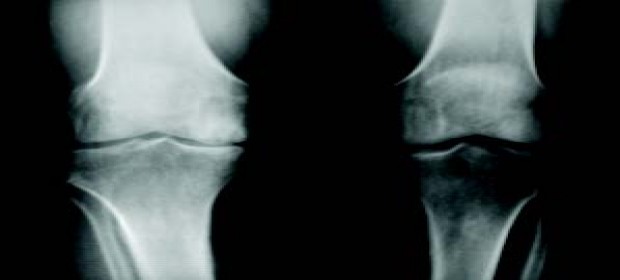

X-rays, MRI, CT Scan